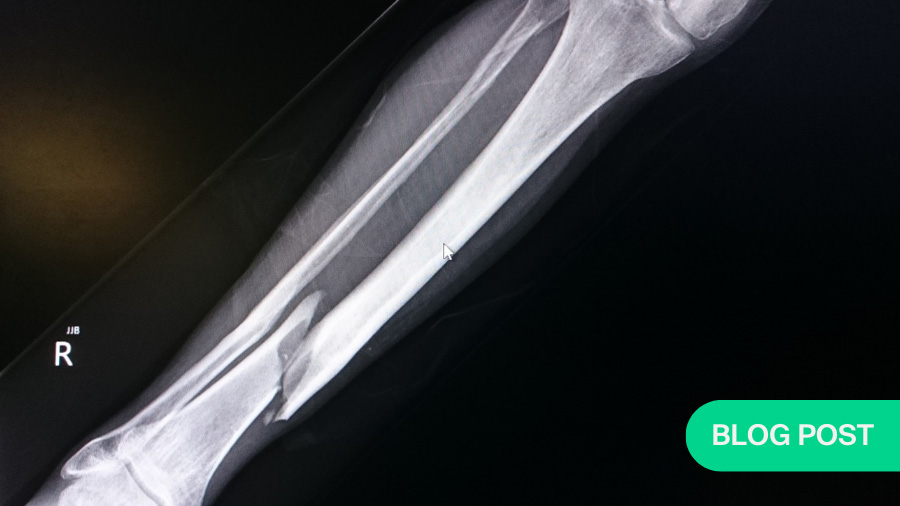

When it comes to the clinical treatment of broken bones, the orthopedic discipline has seen countless advances in recent decades in areas such as fixation and imaging. However, when it comes to tracking and assessing the healing process as it takes place, there remains a clinical gap that all orthopedic surgeons are keenly aware of: we have no quantitative system to reliably measure in a timely fashion how well a broken bone is mending after treatment. Instead, we largely rely on radiographic measurement tools, which are qualitative in nature—surgeons essentially look at x-ray images after an operation to try and determine how much bone callus has formed across the fracture gap.

The problem is that bone heals very slowly, and the deposition of the mineralized tissue that eventually makes up the bone takes place towards the very end of the process. However, the x-ray can only visualize the finished bone, but not its formation. In practical terms, this means that in a patient with, for instance, a tibia fracture that does not heal as expected—as happens in around one in ten cases—we will not be able to identify the problem, much less confidently act on it, until six to nine months after surgery.

There have been various attempts over the years to establish objective methods to better quantify bone healing with the help of tools that translate radiographic images into numbers. For long bones like the tibia, femur, and humerus, perhaps the most noteworthy among these is the modified Radiographic Union Scale for Tibia fractures (mRUST) scoring system. While mRUST has standardized the way we score radiographs, it also requires x-ray images and is therefore not able to speed up the process of assessing the healing process. To put it simply, fracture healing is still judged largely visually, generally qualitatively, and mostly very late.

CXM could also be a great addition to radiography in terms of post-operative protocols because it could allow us to make much more informed decisions. X-ray tells us a lot about how well aligned the bone is, whether the fragments are in the right place, or how well the orthopedic hardware—plates or screws applied during surgery to realign the damaged bone—are staying where they are meant to. CXM levels tell us about the biology: can we allow a patient to walk sooner than we would have felt comfortable otherwise? We never would have known the answer, but now we have something to watch it with.